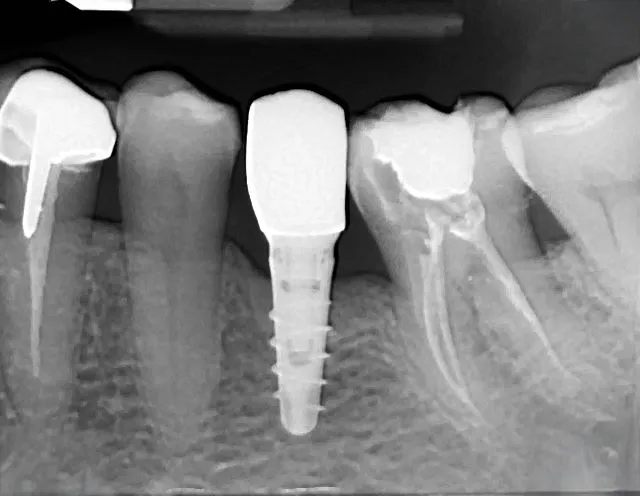

Implantología Guiada 3D

De la tomografía al implante en un solo flujo digital. Con planificación virtual y guías quirúrgicas impresas en 3D, garantizamos la máxima seguridad y exactitud en cada caso.